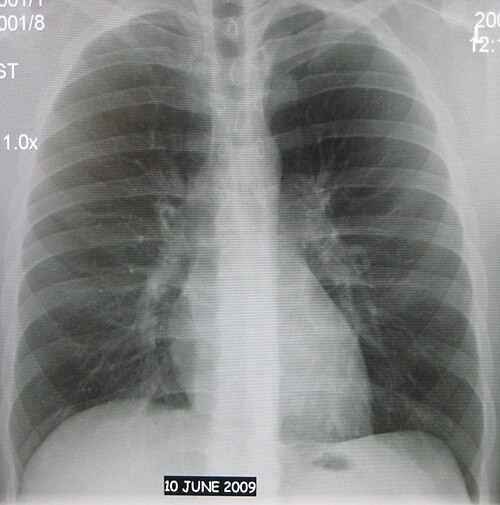

Суть флюорографии заключается в рентгеновском исследовании органов грудной клетки, которое позволяет получить изображение легких, сердца и других структур. Обычно для этого используется специальный аппарат — флюорограф, который делает снимок, минимизируя дозу радиации для пациента. Это исследование считается обязательным в рамках профилактических осмотров, проводимых в рамках медицинских программ. Норма — прохождение флюорографии раз в два года, но для некоторых групп населения, например, для людей, работающих в условиях повышенного риска, она может быть рекомендована чаще.

Суть флюорографии заключается в проведении рентгеновского исследования, при котором специальное оборудование фиксирует изображения внутренних органов, прежде всего легких. Эти изображения, полученные в результате флюорографии, могут выявить различные аномалии, такие как кальцинаты, затемнения, изменения в ткани легких, которые могут указывать на наличие заболевания. Результаты исследования предоставляют врачу ценную информацию для дальнейшей диагностики и назначения лечения.

Процедура флюорографии занимает несколько минут. Пациенту необходимо встать перед аппаратом, расправить плечи и удержать дыхание в момент съемки. Этот процесс абсолютно безболезненный и не вызывает неприятных ощущений. Аппарат делает снимок грудной клетки, на основании которого врач может оценить состояние легких, наличие затемнений, кальцинатов или других патологий. Снимки могут показать, например, признаки воспалений или опухолевых образований, что требует дальнейших клинических исследований.